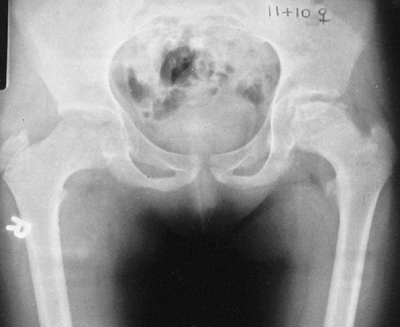

Figure 9.3 Scoliosis (A, B) and protrosia of the hips (E) in a patient with Marfan syndrome. C, D:

Deformity of the apical vertebrae is shown in a three-dimensional reconstruction of a computerized tomographic scan image. (Courtesy of Chris Reily, MD, Vancouver, British Columbia, Canada.) |

Protrusio acetabula is present in about one-third of patients with

Marfan syndrome. It is not related to bone mineral density and is

usually asymptomatic (39), and thus prophylactic fusion of the triradiate cartilage is probably not warranted.

Radiographs of the pelvis usually show various degrees of coxa valga,

and in nearly 20% of patients there is radiographic evidence of

protrusio acetabuli (69,70).